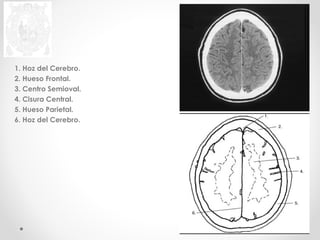

1. Hoz del Cerebro.

2. Hueso Frontal,

3. Centro Semioval.

4. Cisura Central.

5. Hueso Parietal.

6. Hoz del Cerebro.

2. Hueso Frontal.